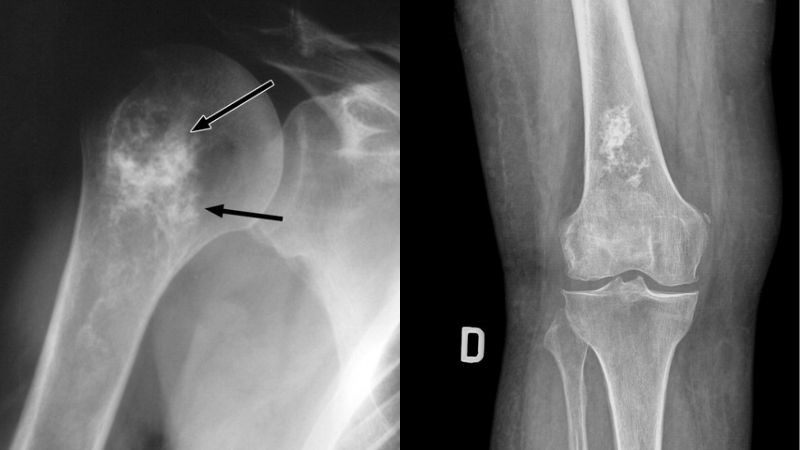

Sau khi được kiểm tra, bạn có thể được đề nghị chụp X-quang vùng bị ảnh hưởng để tìm kiếm bất kỳ vấn đề nào trong xương.

Nếu X-quang cho thấy những vùng bất thường, bạn sẽ được giới thiệu đến bác sĩ phẫu thuật chỉnh hình (chuyên gia về xương) hoặc chuyên gia ung thư xương để đánh giá thêm.

Chụp X-quang nhằm chẩn đoán ung thư xương